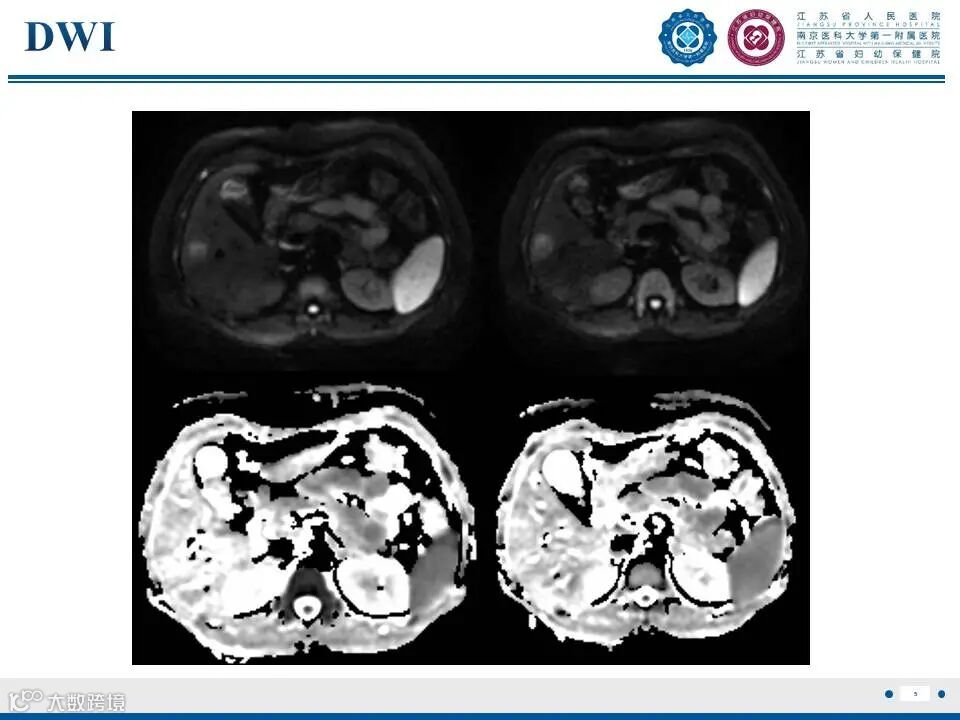

肝脏局灶性结节性增生——非典型瘢痕II影像诊断

肝脏局灶性结节性增生——非典型瘢痕II影像诊断 鼎湖影像